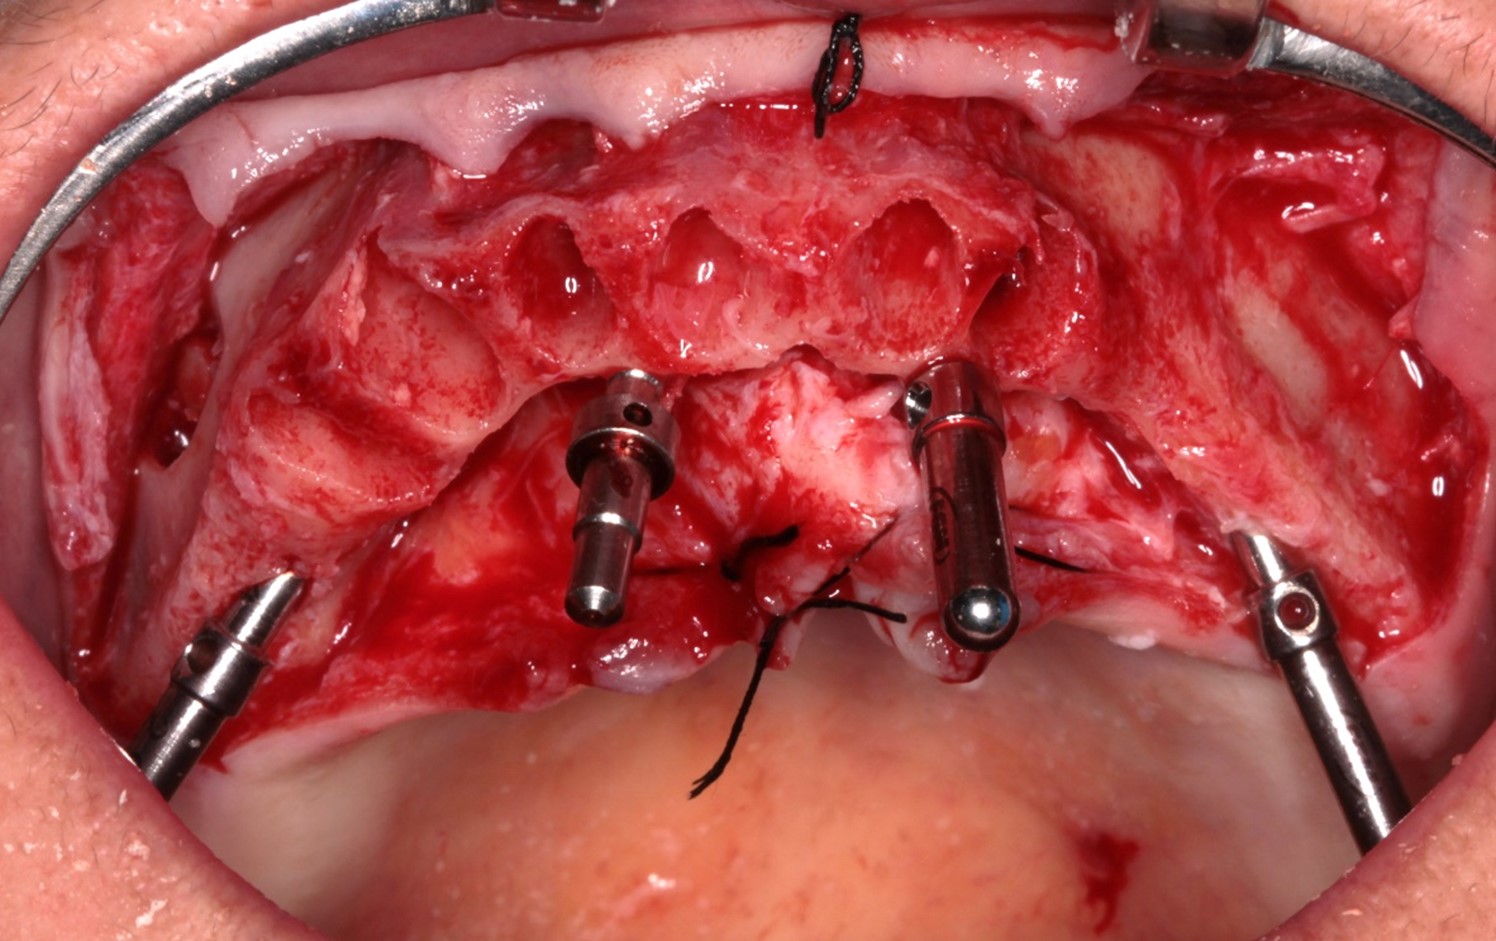

FIG. 03 – Aspecto pós-descolamento do tecido e osteotomia para regularização óssea.

FIG. 04 – Após a perfuração da broca 2.4 e colocação dos paralelizadores para verificar o polígono.